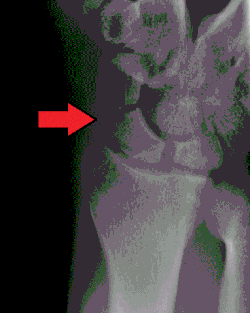

Złamanie kości łódeczkowatej – najczęstsze złamanie kości wśród złamań kości nadgarstka[1].

Tkliwość tabakierki anatomicznej, bolesne odwracanie przedramienia, ból podczas ucisku w osi II kości śródręcza. Obraz RTG często jest niejednoznaczny. Konieczne jest wykonanie RTG w projekcjach: ap, bocznej oraz skośnych. Często konieczne jest powtórzenie RTG po 7–14 dniach lub wykonanie badania metodą tomografii komputerowej (TK).